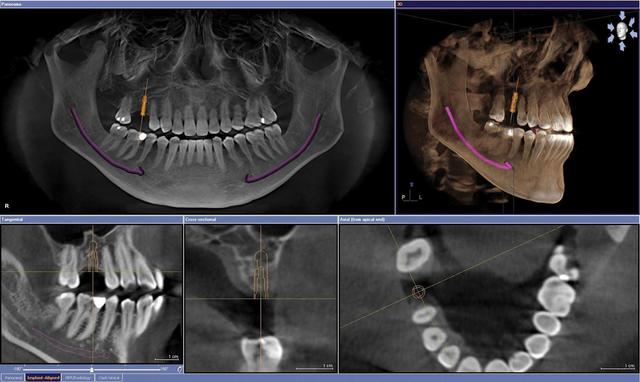

El comienzo de las aplicaciones como la cirugía e implantología guiadas y asistidas por ordenador, introducidas a raíz de los trabajos elaborados en el Proyecto Phidias, comenzado en 1998su difusión mundial, inundándose todo el sector dental con otros productos de los demás fabricantes (i-CAT-ISI, CB-Mercuary-Hitachi, 3D-Accuitomo-JMorita, Picasso-Vatech-Ewoo, Iluma-Kodak, Galileos-Sirona, Planmeca,etc.).

NUEVOS SISTEMAS DE TAC DENTALES

Estos han son herramientas muy especializadas para la planificación en cirugía e implantología

SimPlant (de Materialise)

NobelGuide-NobelClinician (de NobelBiocare)

CAD Implant

Implant Guidance-Denx

iGuide

Implant Master

Scan2Guide

Compu Guide

Implant3D

Maxilim MSPS

Oralim OIPS